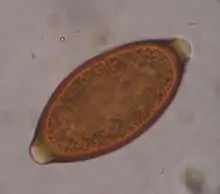

Trichuris vulpis is a whipworm that lives in the large intestine of canines in its adult stages. Out of different types of worms, Trichuris vulpis is one of the smaller worms with a size ranging from 30–50 mm in length. As the name suggests, the worm has a whip-like shape with distinct features including a small, narrow anterior head, which is the digestive part of the worm, and a larger posterior tail, which is the reproductive part of the worm. Eggs from T. vulpis are oval shaped with bipolar plugs and contain a thick outer shell. Their sizes range from 72–90 μm in length and 32–40 μm in width.[1] Because of their thick outer shell, T. vulpis eggs are very resistant to environmental extremes such as freezing or hot temperatures, thus allowing for their long viability in the outside world.[2]

Infection of this parasite can be confirmed with detection of eggs in the canine's feces. Adult T. vulpis females can produce more than 2,000 eggs per day. These eggs can be detected in the canine's feces by the fecal flotation method.[14] This method utilizes the differences of specific gravity of eggs, fecal debris, and the flotation solution.[15] Although these eggs are dense, the use of proper fecal flotation technique using a sugar solution and centrifugation can increase the chances of identifying these eggs in a fecal sample.[16] Multiple fecal samples may need to be tested as the eggs may be shed periodically.[17]